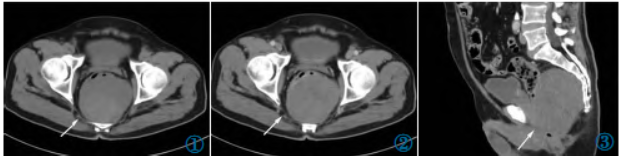

2 年前患者因发现右侧腹股沟区包块12 天再次入院。查体右侧腹股沟区可见触及肿物大小约3 cm×2 cm,质韧,边界尚清楚,活动度较差。腹部CT 增强(图4~6)示右侧腹股沟区可见类圆形软组织结节,大小约2.8 cm×2.3 cm,边缘尚清楚,平扫CT 值约31 HU,增强扫描静脉期CT 值约40 HU,肿物强化不明显,中央呈相对低密度。行超声引导下穿刺活检术,病理诊断为胃肠间质瘤(Gastrointestinal stromal tumor,GIST)。

图4~6 腹部CT 平扫轴位、静脉期轴位及矢状位图像示右侧腹股沟区类圆形软组织结节。

免疫组化结果:CD117(+),DOG-1(+),Vimentin(+),CD34(+),Ki-67(阳性细胞数40%)图(7,8);基因检测结果:c-kit 基因11 外显子点突变。遂继续予以口服甲磺酸伊马替尼(格列卫)400 mg/d,服药后肿物逐渐缩小至稳定,1 年前腹部CT 平扫(图9)示大小约2.4 cm×1.7 cm。